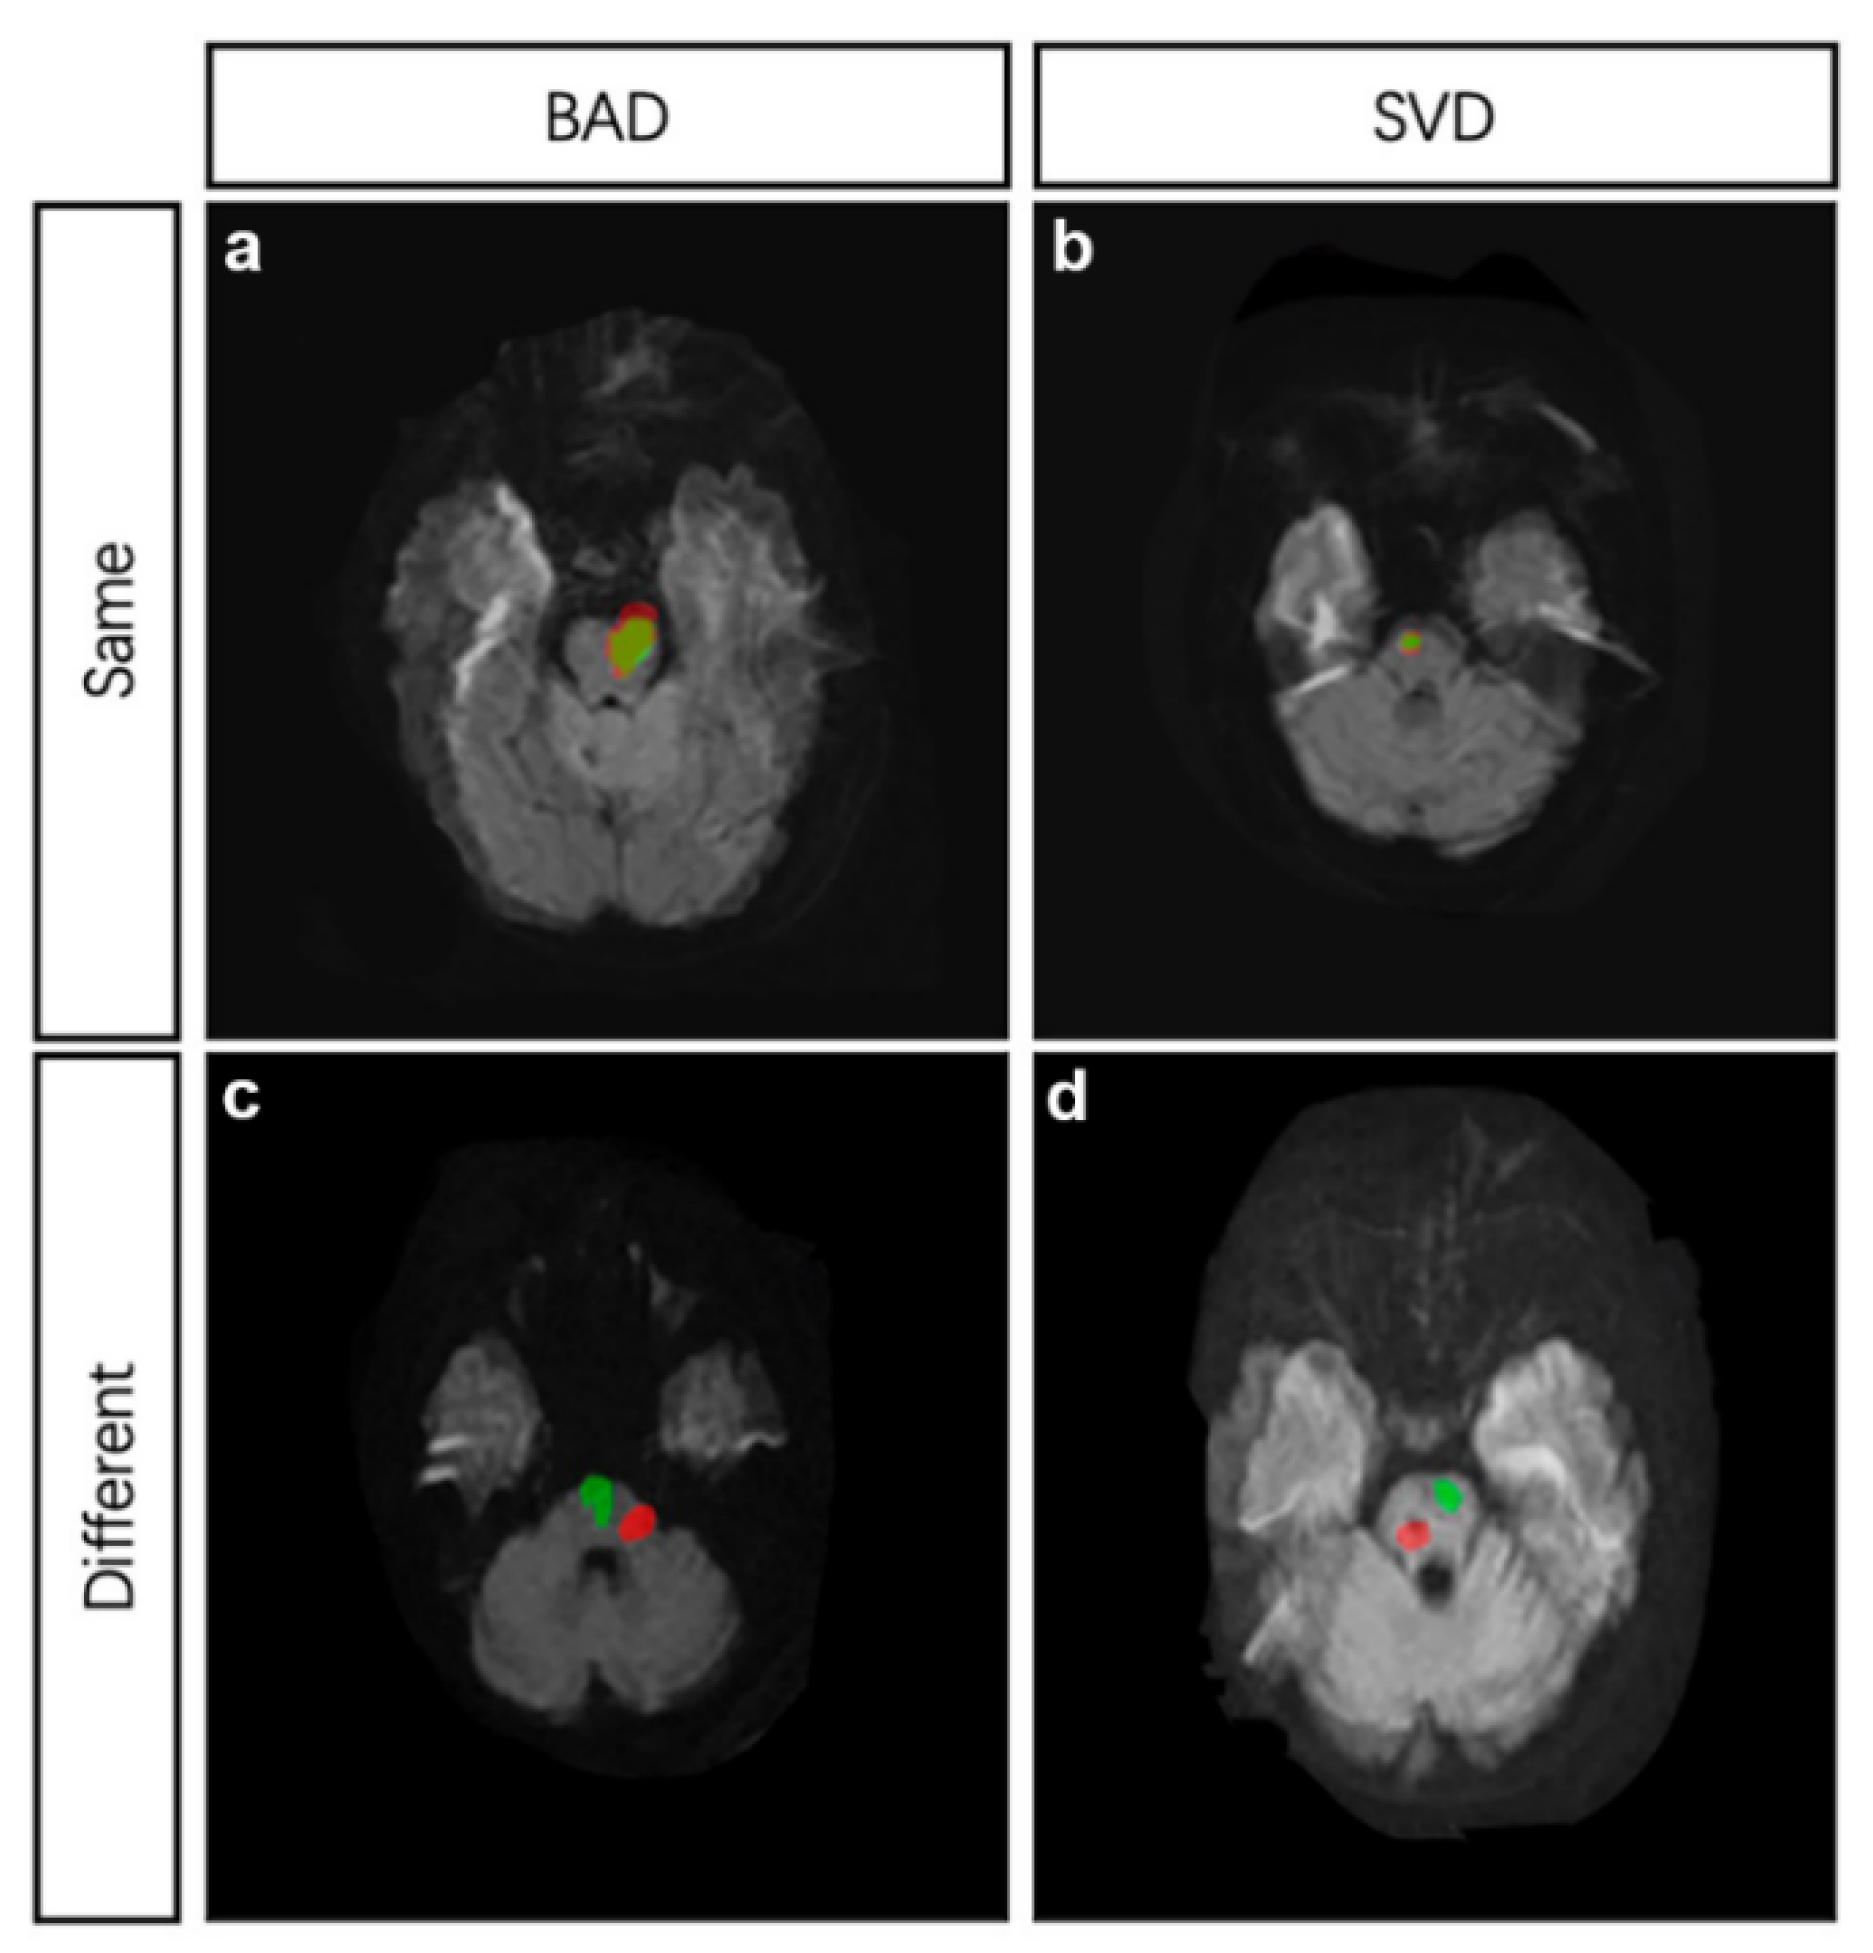

2.4. The Site and Mechanisms of Pontine Infarction

| Mechanism of Index Pontine Infarction | p | ||

|---|---|---|---|

| BAD | SVD | ||

| N | 37 | 30 | |

| Mechanism of recurrent pontine infarction located at the same site with index stroke | <0.05 | ||

| BAD | 26 | 4 | |

| SVD | 1 | 10 | |

| Mechanism of recurrent pontine infarction located at different sites with index stroke | <0.05 | ||

| BAD | 4 | 8 | |

| SVD | 6 | 8 | |